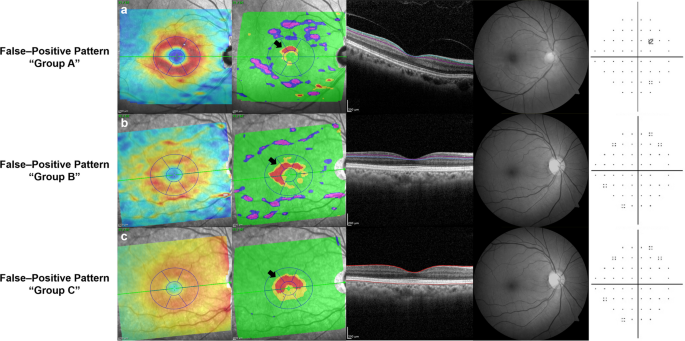

The patterns of false-positives on the segmented macular layers deviation maps were classified into 3 groups according to the shape and area of the abnormal color-coded area: group A (island shape circumpassing less than 180° in area) (Fig. 3a); group B (hook shape circumpassing more than 180° but less than 360° in area) (Fig. 3b); group C (donut shape around inner annulus, circumpassing 360° in area) (Fig. 3c). As for the determination of the false-positive-pattern groups, we found almost perfect interobserver agreement (kappa = 0.878 for GCL, 0.855 for IPL, and 0.891 for retinal layer, all ps < 0.001). Figure 4 reveals the true glaucomatous structural damage on the segmented macular layers and RNFL deviation maps.

False-positive patterns on deviation maps of segmented macular layers on Spectralis OCT. Each labeled row (a–c), from left to right, consists of a thickness map, a deviation map, a corresponding B-scan with colored lines demarcating the segmented layer, red-free retinal nerve fiber layer (RNFL) photography and Humphrey (Carl Zeiss Meditec, Dublin, CA, USA) C24–2 visual field. (a) Healthy eye of 58-year-old female with pattern group A (island shape circumpassing less than 180° in area) on ganglion cell layer (GCL) deviation map. (b) Healthy eye of 66-year-old female with pattern group B (hook shape circumpassing more than 180° but less than 360° in area) on inner plexiform layer (IPL) deviation map. (c) Healthy eye of 66-year-old female with pattern group C (donut shape around inner annulus, circumpassing 360° in area) on retinal layer deviation map.